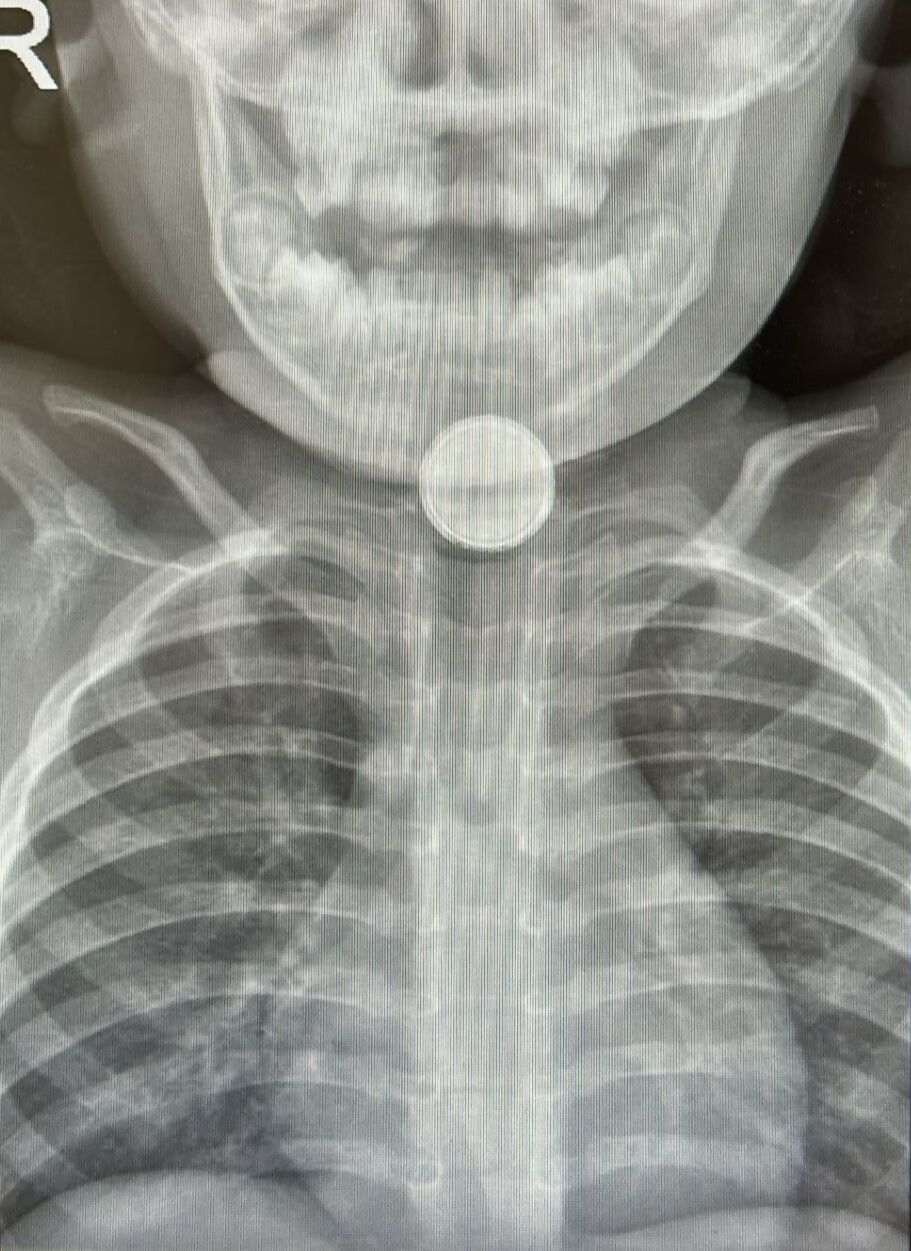

الدكتور منير أبو هاشم، أخصائي الطب الباطني في كلاليت، لواء حيفا والجليل الغربي، يوضح: “عندما تعلق البطارية في المريء، تبدأ في إحداث تفاعل كيميائي سريع يؤدي إلى تلف خطير في الأنسجة خلال أقل من ساعة. وقد يشمل الضرر حروقًا عميقة، وثقوبًا في جدار المريء، ونزيفًا داخليًا خطيرًا، وأحيانًا أضرارًا مزمنة تستمر حتى بعد إزالة البطارية من الجسم. التدخّل الطبي العاجل والمبكر هو عامل حاسم في تحسين فرص النجاة والتعافي“.

- في المستشفى، سيتم إجراء تصوير بالأشعة لتحديد مكان البطارية واتخاذ الإجراءات الطبية اللازمة.